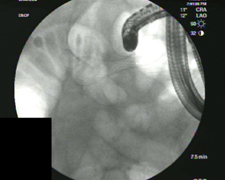

Photo of stint from endoscopic camera

Stent placed in the bile duct